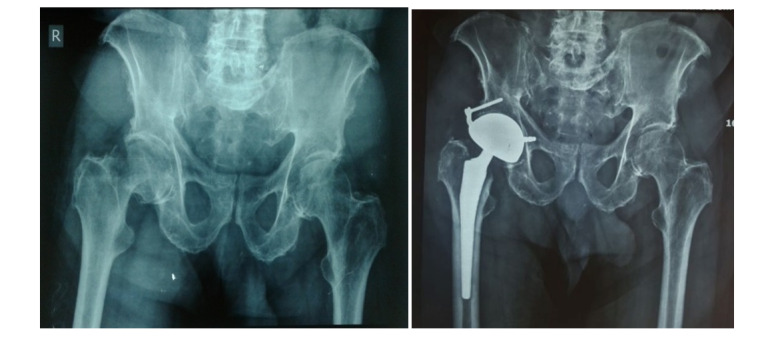

Background: With the increase in life expectancy and the rising number of total hip arthroplasty (THA) cases, the rate of complications is also expected to increase. One of the most challenging complications is dislocation, which is the leading cause of revision surgery within the first year after THA. This study aimed to assess hip instability rates in high-risk patients who underwent dual mobility cup (DMC) implantation.

Methods: This retrospective study reviewed all patients who underwent THA with DMC at Rasul-e-Akram Hospital between 2014 and 2021. DMC was used in high-risk patients for dislocation, including those with neuromuscular diseases (e.g., Parkinson's disease, poliomyelitis) and intracapsular femoral neck fractures (FNF), instead of the standard cup. Clinical outcomes, instability, and other complications were recorded. All data was analyzed using SPSS software version 27.0.1. The chi-squared test was used to compare binary variables, and the student's t-test was used to compare numerical variables after checking for normal distribution.

Results: A total of 163 patients (168 hips) underwent THA with DMC, with a mean age of 58 ± 5.3 years. Five patients had bilateral total hip surgery. The average follow-up time was 48 ± 5.8 months. The average BMI of patients was 28.3 ± 3.1. The preoperative Harris Hip Score (HHS) was 49 ± 8.5, while the postoperative HHS at the four-year follow-up was 89 ± 2.4. None of the patients experienced a dislocation requiring revision, and One case of severe wear on the polyethylene's inner surface and intraprosthetic dislocation, without a dislocated metal head, was identified and revised. No cases of component loosening or significant osteolysis were observed.

Conclusion: The use of DMC can significantly reduce the dislocation rate in patients with risk factors such as femoral neck fractures while improving patient satisfaction and restoring near-normal function. We recommend greater consideration of this cup in patients at risk of dislocation.